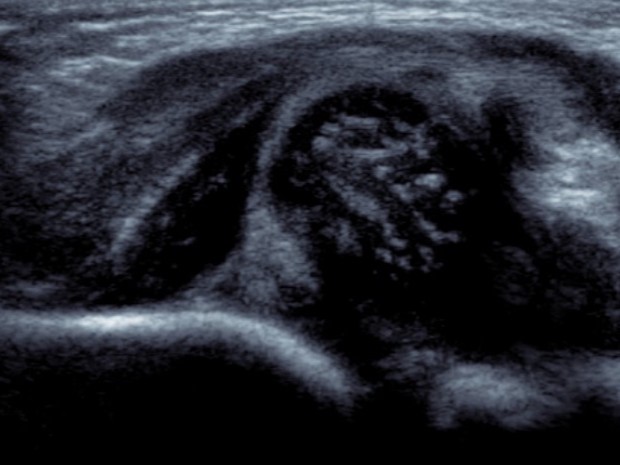

Dislocated hip on ultrasound